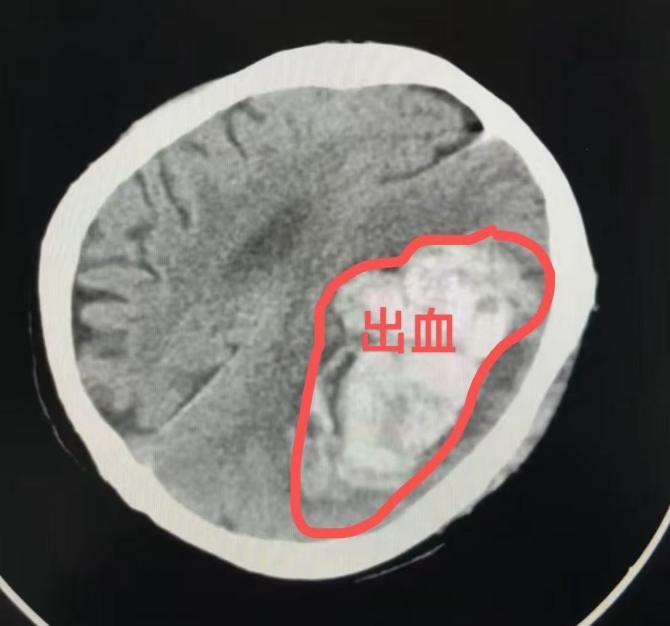

王阿婆被紧急送到北仑区人民医院时,已处于昏迷不醒,呼之不应的状态。头颅CT检查显示颅内存在大面积出血,严重危及生命安全。神经外科团队阅片后评估,出血量已达上百毫升。待急诊完善头颅CTA排除颅内血管畸形等特殊情况后,王阿婆被紧急送入手术室,在医护团队的默契配合下,手术顺利完成,生命体征平稳后被送入重症监护室,目前正在康复中。

出血性脑卒中